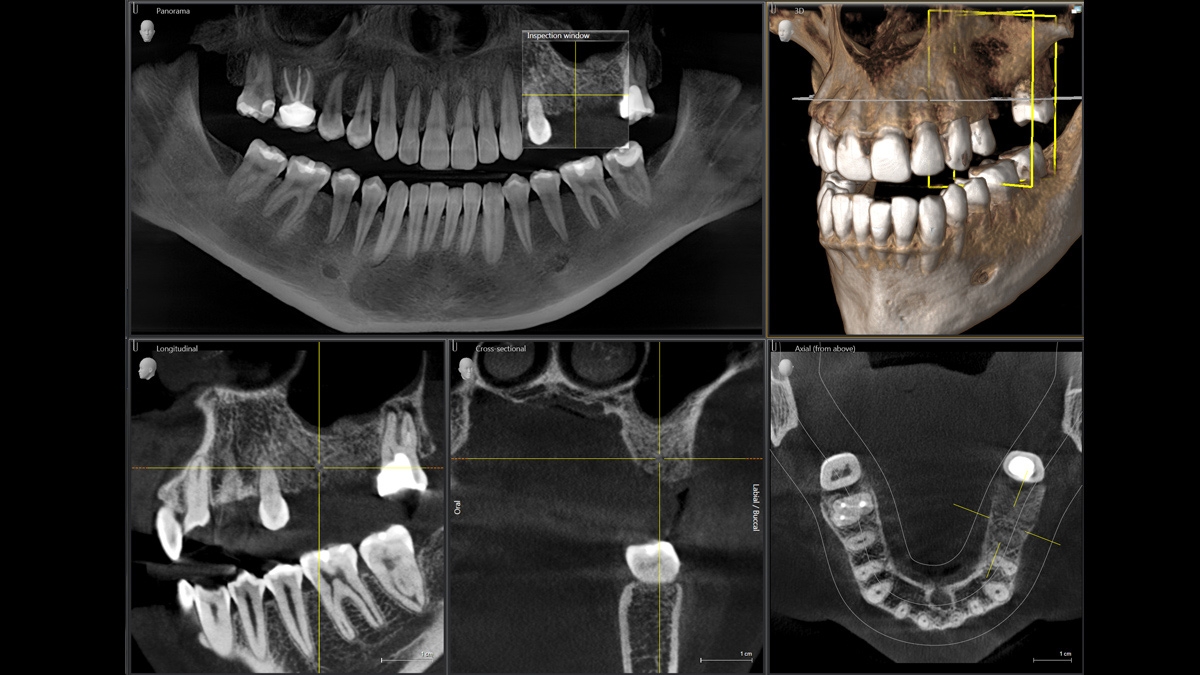

Les artéfacts métalliques représentent un défi pour la radiographie 3D. Lors de la reconstruction tridimensionnelle, les objets radio-opaques créent des ombrages et des effets de stries et perturbent ainsi l‘évaluation. MARS réduit automatiquement les artéfacts métalliques et facilite ainsi l‘évaluation.

MARS maintient autant que possible les structures anatomiquement pertinentes exemptes d‘artéfacts.